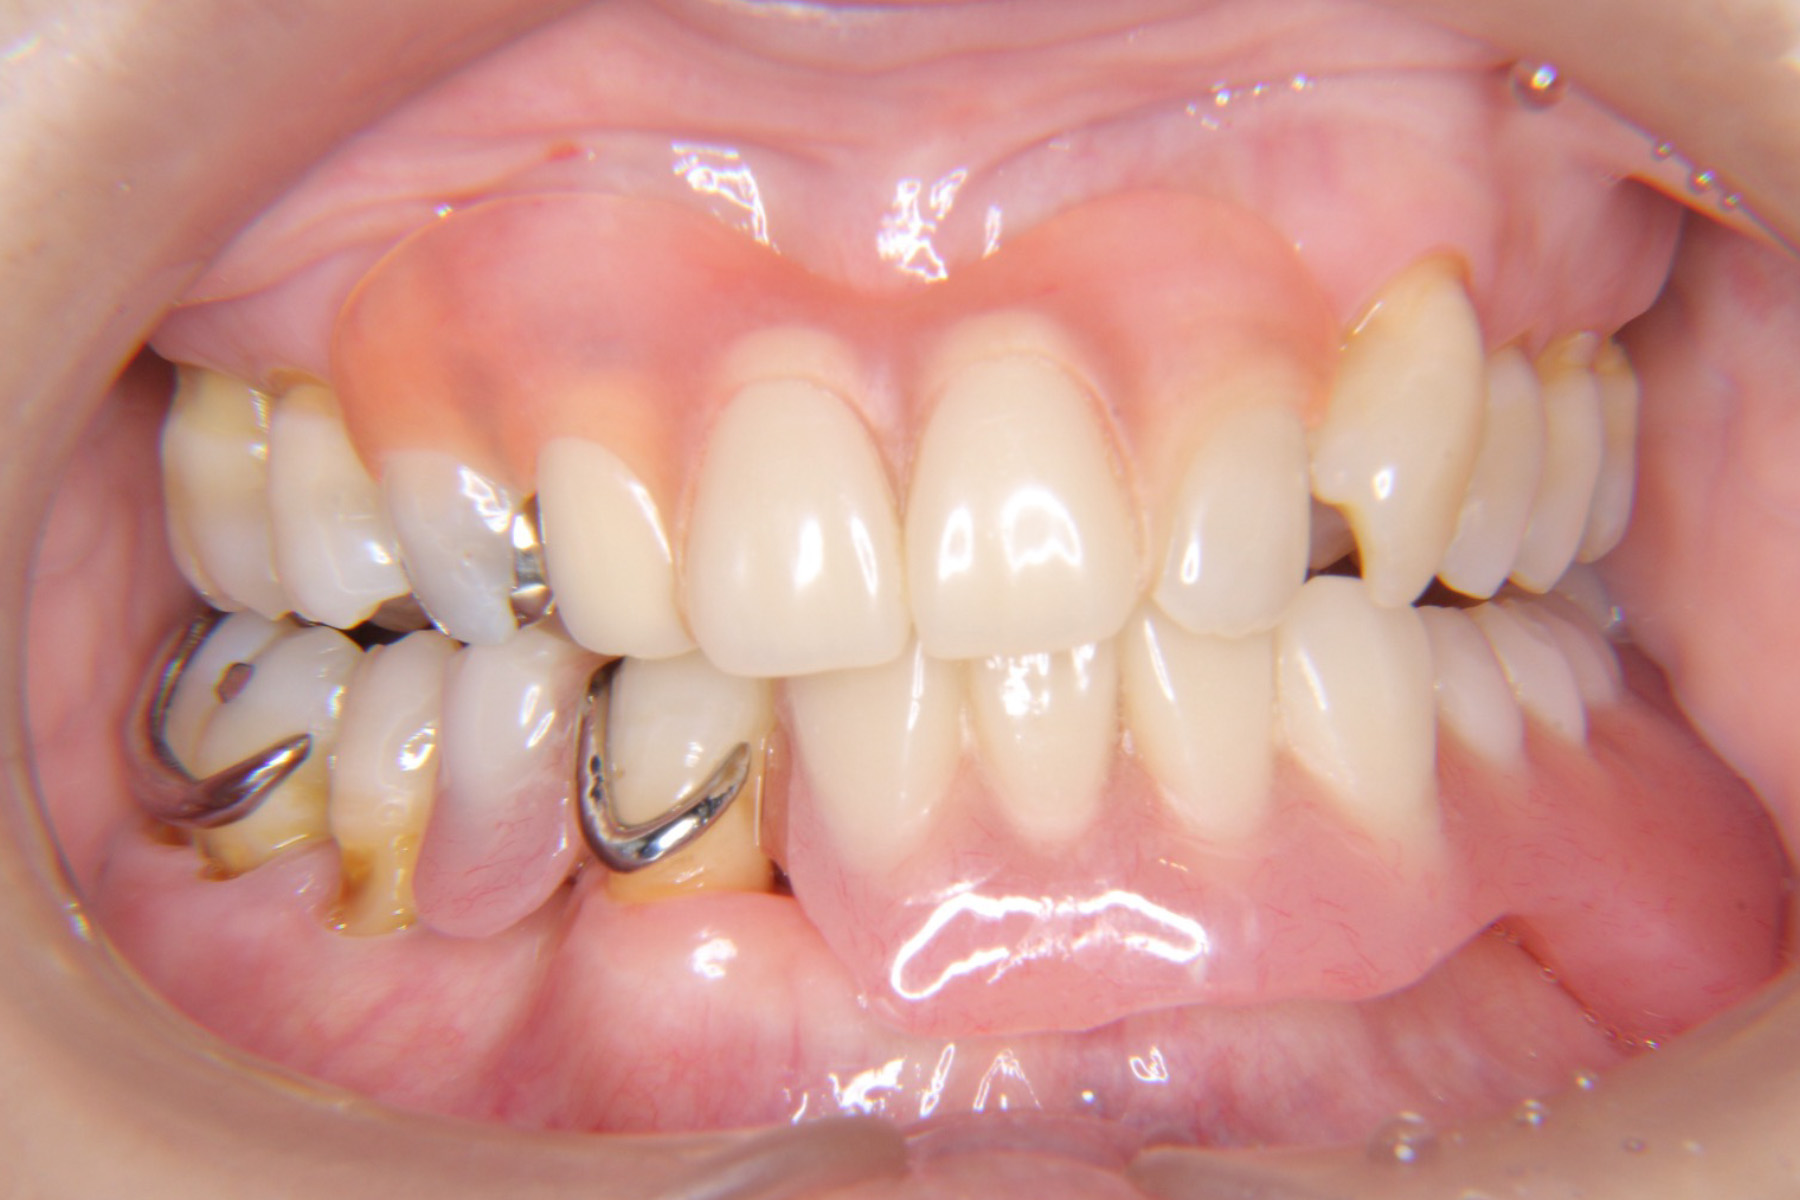

CASE19:入れ歯の

症例

CASE19

CASE20:入れ歯の

CASE20

CASE21:入れ歯の

CASE21